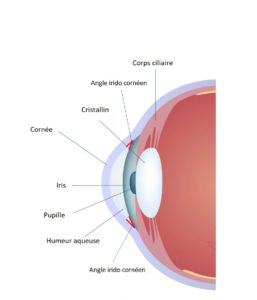

Le corps ciliaire situé juste en arrière de l’iris produit un liquide transparent nommé humeur aqueuse qui circule en avant du cristallin et de l’iris dans ce qui est appelé la chambre antérieure. L’évacuation de ce liquide se fait par l’angle irido cornéen (situé entre l’iris et la cornée) au travers d’un filtre nommé le trabéculum.

Il peut exister un obstacle au passage de l’humeur aqueuse lorsque l’iris est particulièrement dilaté (la nuit). On parle alors de glaucome par fermeture de l’angle.

Lorsqu’il n’y a aucun obstacle en amont du trabéculum mais que ce dernier présente une résistance anormalement importante au passage de l’humeur aqueuse, une élévation de la tension oculaire, apparait qui engendre le glaucome à angle ouvert.